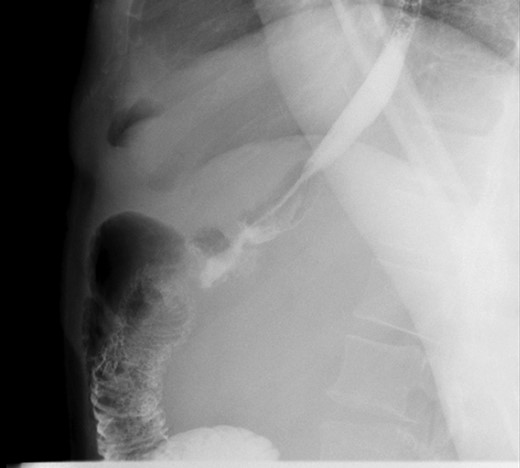

A 44-year-old female with BMI 25.5 with history of hepatic cirrhosis, upper GI bleed, GERD underwent LRYGB in March 2016, ventral hernia repair 2016. She presented to the clinic 1 year post 81 pounds weight lost since surgery with chronic colicky abdominal pain associated with nausea and vomiting. Vital signs were stable. On physical exam, she had tenderness in the right side of her abdomen and epigastric area. All the labs findings were unremarkable. Prior to this visit patient had an esophagogastroduodenoscopy (EGD) which was also negative. CT scan of abdomen shows hepato-splenomegaly with periappendiceal fat stranding and dilated appendix. Patient was taken to the operating room for diagnostic laparoscopy and appendectomy in April 2017 and was found to have candy cane syndrome. We resected excessive redundant (4 cm length) of the long blind jejunal loop of gastrojejunostomy anastomosis using Endo GIA Tri-Stapler device. Post-operative patient had upper GI which was normal (Figs 1 and 2). Post-operative course was uneventful. The patient was discharged to home on post-operative Day 2 and returned to clinic 2 weeks for follow up and tolerating diet and completely pain free.